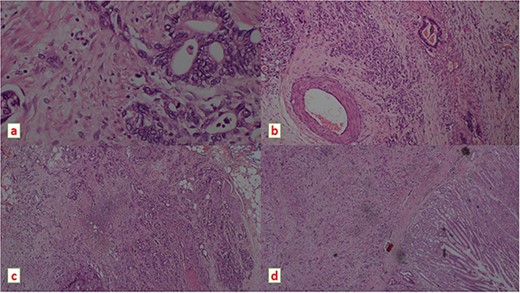

A decision to proceed with surgery was made following a discussion with the multidisciplinary team. She was optimized to the best and a distal gastrectomy with limited lymph node clearance was performed. Following surgery, her lactate levels settled down progressively and she improved clinically within 48 h (Fig. 2). The histology of the resected specimen revealed adenocarcinoma (Fig. 3).

Histopathology images showing moderately differentiated adeno carcinoma on H & E stain under light microscope, (a) magnification ×400 (b) ×100 demonstrating a vascular emboli (c) magnification ×100 demonstrating peri neural invasion (d) magnification ×40.